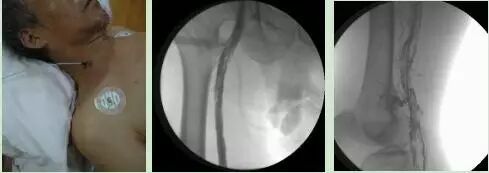

下肢深静脉血栓的腔内微创治疗,手术创伤小,治疗全程仅一穿刺针眼,大大减少了患者的痛苦,溶栓彻底,大大降低了下肢深静脉血栓后遗症的发生率。

下肢动脉硬化闭塞症的腔内及杂交手术治疗杂交手术治疗动脉硬化闭塞症

腔内支架植入术开通下肢血管

主动脉夹层的介入治疗